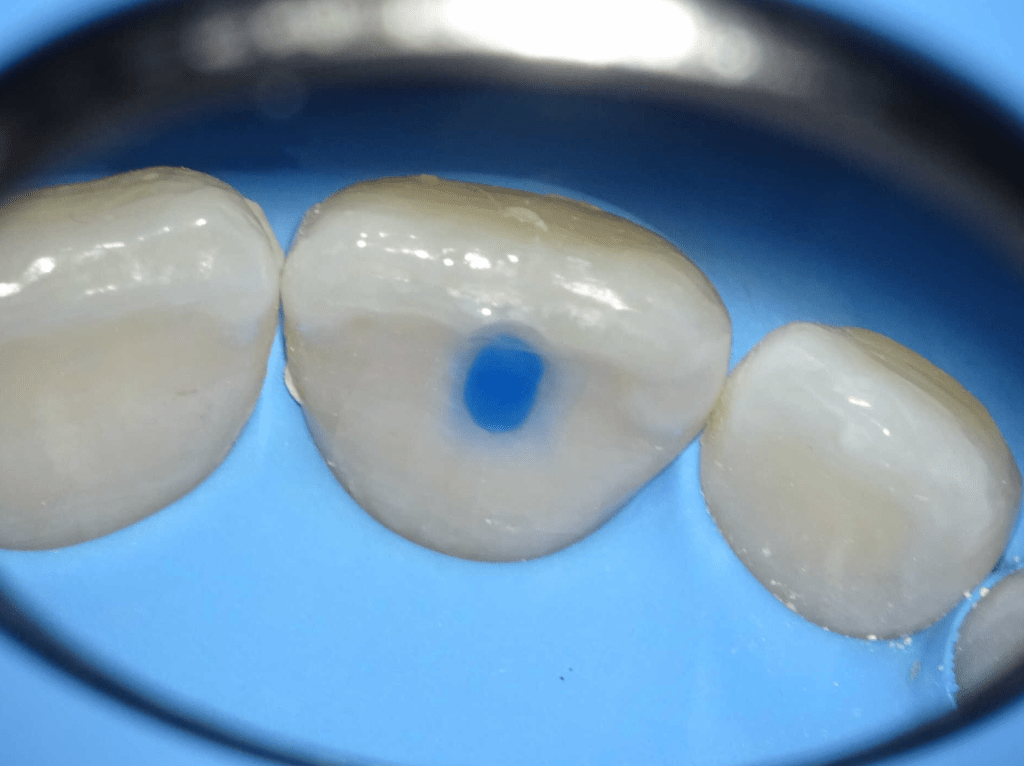

Acceso ultraconservador a través de incrustación reciente